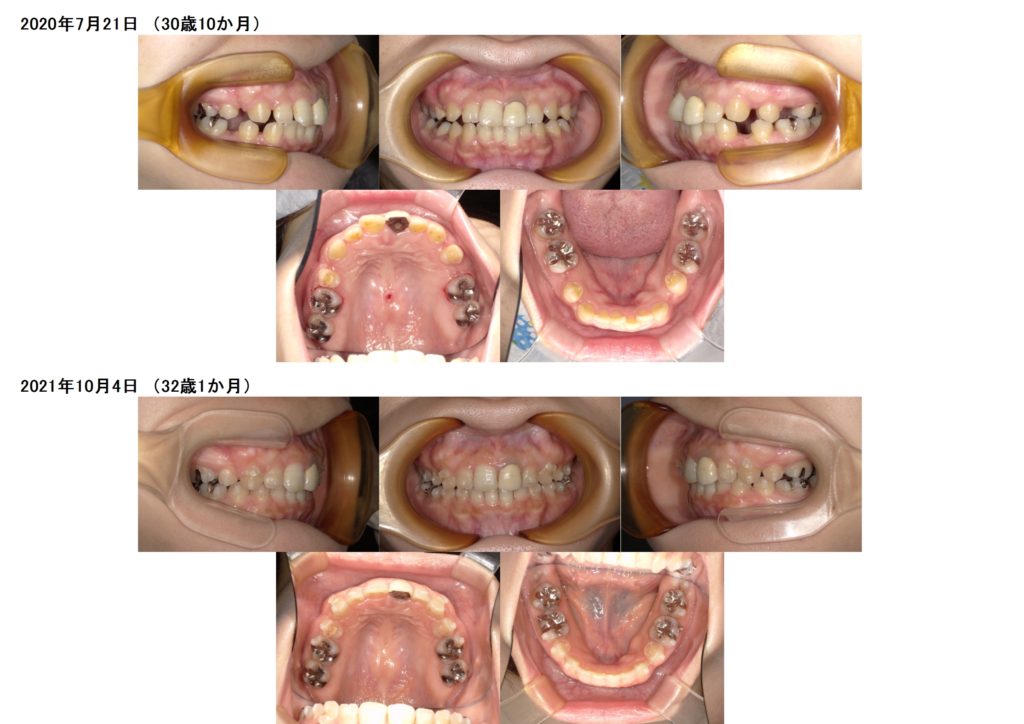

今回は、マウスピースでの治療例です。

上の歯に乳歯が残っているので、その乳歯の抜歯と、その他永久歯を3本抜歯しての治療になります。

土台を維持しつつ、抜歯したスペースを4か月間動かしました。

随分と歯が動いたのが分かりますよね☆

その後、マウスピースの治療に移ります。

抜歯した隙間も、前歯の位置も変化したのが分かると思います。